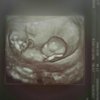

Cudna. Zazdroszczę [emoji4]Jesteśmy po wizycie, z dzidziusiem wszystko w porządku, pobrali mi jeszcze krew do testu Pappa i za 10 dni mają być wyniki. Jestem juz spokojniejsza bo się bałam. Zobacz załącznik 808760

Prawdopodobnie będzie dziewczynka [emoji7]

cudowne wieściJesteśmy po wizycie, z dzidziusiem wszystko w porządku, pobrali mi jeszcze krew do testu Pappa i za 10 dni mają być wyniki. Jestem juz spokojniejsza bo się bałam. Zobacz załącznik 808760